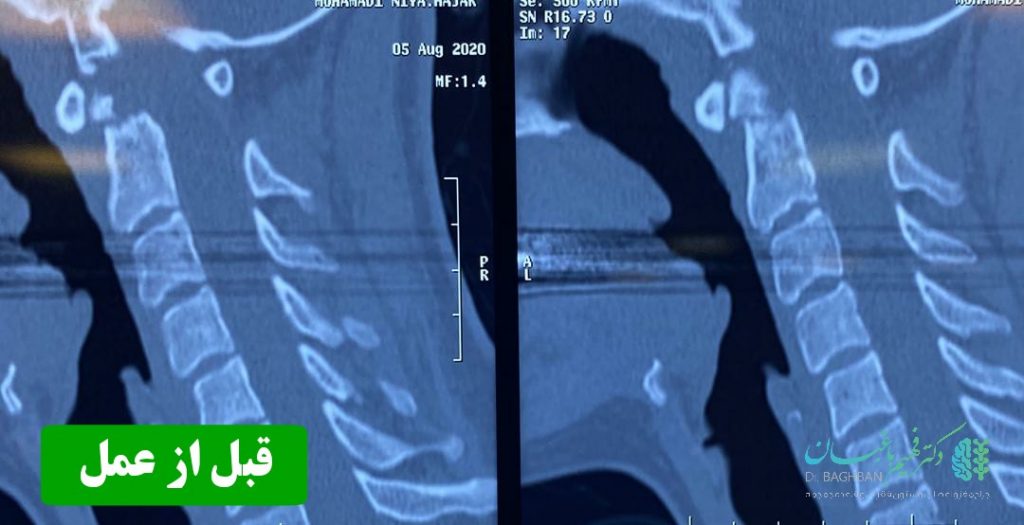

بیمار خانم جوان با سابقه ضربه شدید گردن و شکستگی زائده ادونتویید مهره دوم گردن که تحت عمل جراحی قرار گرفتند. تصاویر قبل و بعد از عمل را در زیر مشاهده می نمایید . همچنین توضیحات دکتر باغبان را در حین جراحی در ویدئوی انتهای مقالات مشاهده کنید. (ویدئو حاوی تصاویر جراحی می باشد)

تصاویر قبل از عمل